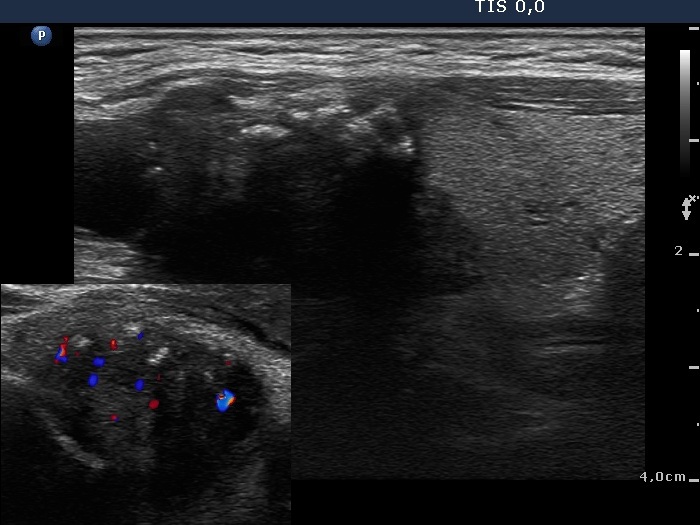

Granulation around surgical thread (histological diagnosis) - case 411 |

Papillary carcinoma (histological diagnosis) - case 779 |

Here is another example of the differential diagnostic problem caused by granulation around surgical thread. Again, there is no difference between the ultrasound presentations of these cases except for the vascularization. The right, malignant case cannot be a granulation around surgical thread which is always avascular; however, this is not a great revelation in a patient who has not been operated. Conversely, the lack of vascularization by no means excludes the possibility of a carcinoma.